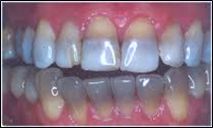

Dentinogenesis imperfecta

Front

Back